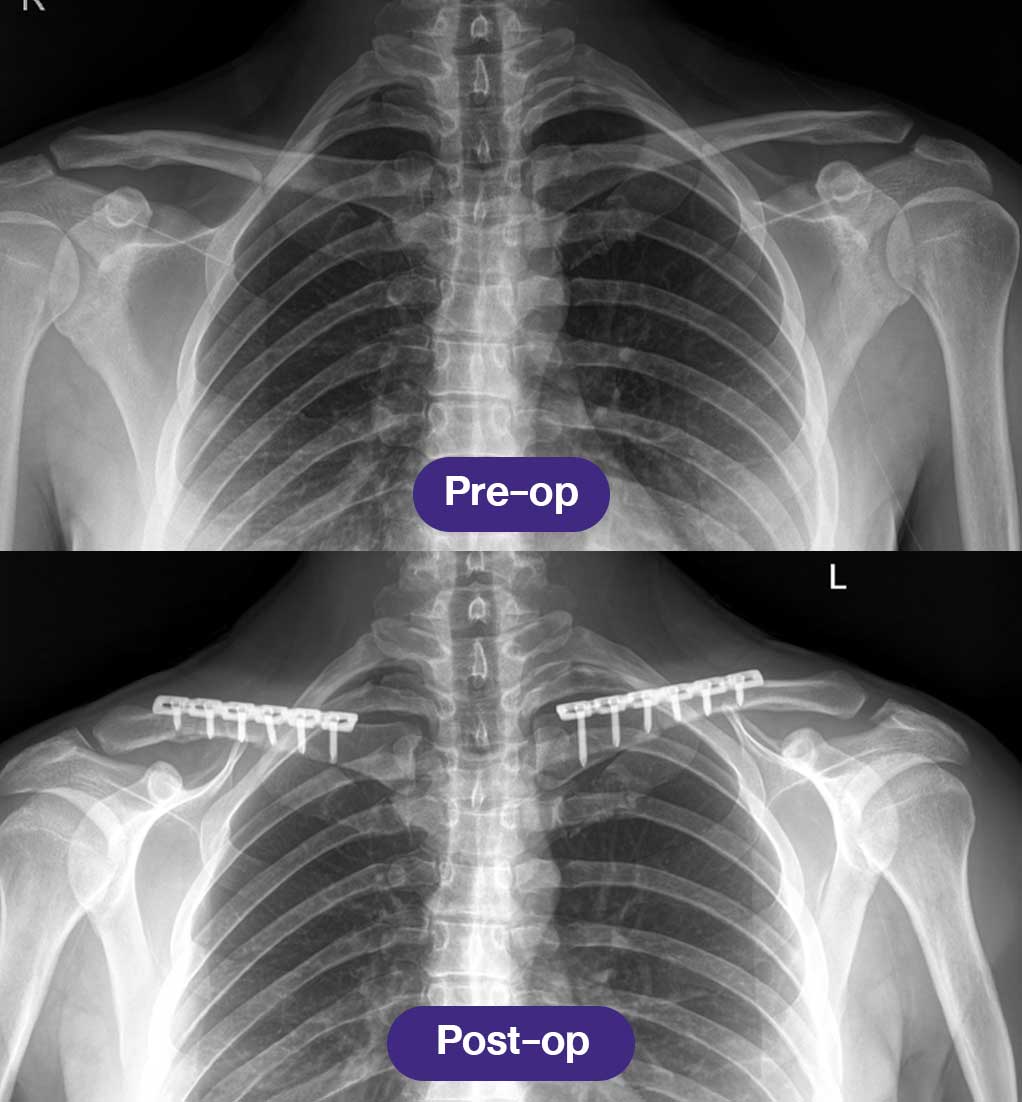

📌 การเอกซเรย์กระดูกไหปลาร้าหลังการผ่าตัด จะดำเนินการเป็นประจำในการติดตามผลครั้งแรก เพื่อยืนยันการจัดแนวของกระดูกที่เหมาะสมและความคืบหน้าของการสมานตัว

การเอกซเรย์หลังการผ่าตัดและคำแนะนำหลังการผ่าตัดลดความกว้างหัวไหล่

- การเอกซเรย์กระดูกไหปลาร้าหลังการผ่าตัด จะดำเนินการเป็นประจำในการติดตามผลครั้งแรก เพื่อยืนยันการจัดแนวของกระดูกที่เหมาะสมและความคืบหน้าของการสมานตัว